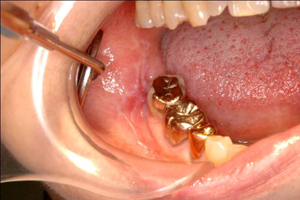

フコイダン著効例 (右側歯肉頬粘膜扁平苔癬)

フコイダン投与 前日 BEFORE

フコイダン投与 1ヶ月後 AFTER